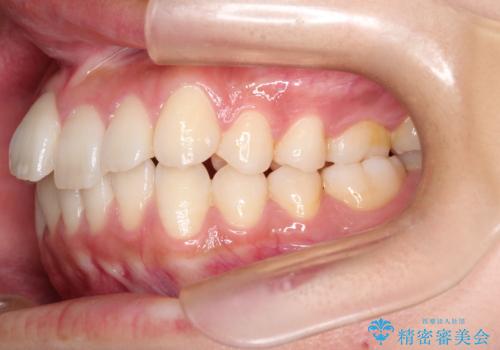

前歯の叢生・Ⅱ級咬合を改善|TADを用いた遠心移動+インビザライン矯正

- 前歯のガタガタと臼歯関係のⅡ級(上顎の歯列が前方にある状態)を改善するため、TAD(歯科矯正用アンカースクリュー)を使用したインビザライン矯正を計画しました。まずTADを上顎の適切な位置に設置し、それを固定源にして奥歯を後方(遠心)へ移動させ、十分なスペースを確保します。その後、インビザラインによるマウスピース矯正で前歯の歯列を整え、臼歯関係を正常化します。治療期間はおよそ1年半〜2年を想定しています。

前歯部の叢生(ガタガタ)と臼歯関係のズレを改善するため、抜歯をせずに奥歯を後方へ移動(遠心移動)させることを選択しました。TADという小型のアンカースクリューを顎骨に設置することで、確実かつ効率的に奥歯を後方へ移動させました。併せて透明で目立ちにくいインビザラインを用いることで、審美性を保ちながら治療を進めることが可能でした。患者様の負担が少ないマウスピース矯正と固定源のTADを組み合わせることで、抜歯することなく歯並びと噛み合わせを大幅に改善でき、大変ご満足いただけました。